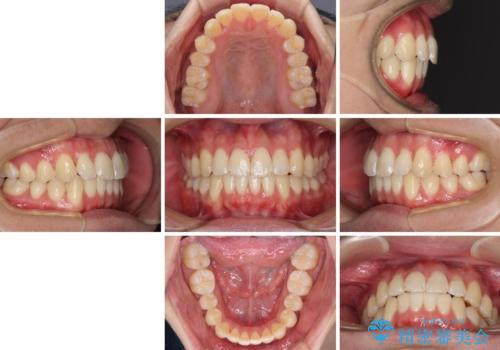

- 前歯のデコボコと若干口元が突出していることを気にして来院された患者様です。

全体的に軽微な叢生が認められ、口元もやや前方に突出していたため、インビザラインでのIPR(歯と歯の間を削る)と歯列全体の後方移動によって歯並びを整えることとしました。

上下ともに歯列の幅が狭かったため、側方に拡大することで前歯のデコボコや突出感を解消するためのスペースを獲得することができました。

歯並びが改善したことはもちろん、咬み合わせの改善まで実感することができ、患者様には大変満足していただけました。